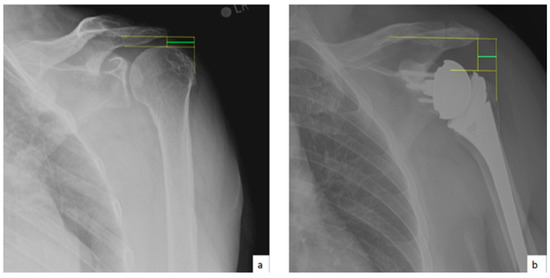

AHD was measured by calculating the perpendicular distance between the most lateral portion of the undersurface of the acromion and a line parallel to the superior border of the greater tuberosity [21] (Figure 1). LHO was measured by determining the distance from the AHD line to the most lateral projection of the greater tuberosity [21] (Figure 2). LSA was measured by drawing a line from the superior glenoid tubercle to the most lateral border of the acromion and a second line from the most lateral border of the acromion to the most lateral border of the greater tuberosity. The angle between these two lines formed the LSA [20] (Figure 3a). DSA was measured by drawing a line between the most lateral border of the acromion and the superior glenoid tubercle and drawing a second line to connect the superior glenoid tubercle with the most superior border of the greater tuberosity. The angle between these two lines formed the DSA [20] (Figure 3b). Glenoid and baseplate were determined as the angle between the floor of the supraspinatus fossa and the glenoid fossa [25] (Figure 4). COR was measured by determining the best fit circle flush to the articular surface, identifying the center of the circle in the humeral head, and then measuring the distance of the perpendicular line between the center of the humeral head and the midpoint of the line connecting the superior and inferior glenoid tubercles [24] (Figure 5b). CSA was measured by a line from the superior pole to the inferior pole of the glenoid and a line from the inferior pole to the lateral edge of the acromion [26] (Figure 5a). In addition, scapular notching was graded according to the Nerot–Sirveaux classification and severity of preoperative cuff tear arthropathy was evaluated according to the Hamada classification [27,28].

Figure 1.

(a) Preoperative acromiohumeral distance (AHD; green line); (b) postoperative acromiohumeral distance (AHD; green line).

Figure 2.

(a) Preoperative lateral humeral offset (LHO; green line); (b) postoperative lateral humeral offset (LHO; green line).